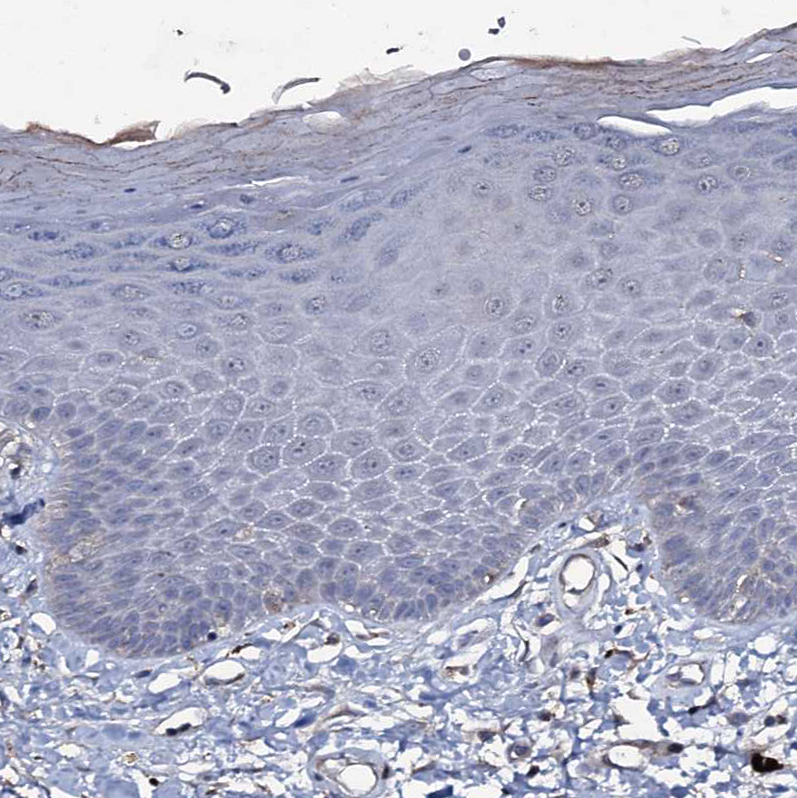

Immunohistochemical staining of human fallopian tube shows strong positivity in cilia in glandular cells.